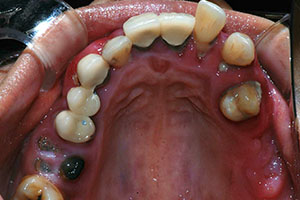

치료증례 전후사진

Before & After